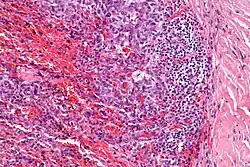

| Micrograph showing an angiomatoid fibrous histiocytoma. H&E stain. |

It is characterized by cystic blood-filled spaces and composed of histiocyte-like cells. A lymphocytic cuff is common. It often simulates a vascular lesion, and was initially described as doing this.[1]